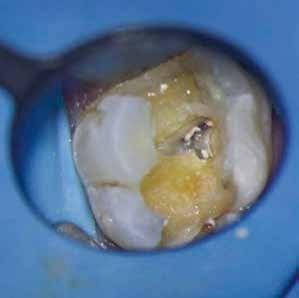

1. a–f ábrák: A cingulumon keresztül gömbfúróval kialakított hozzáférés a trepanációs kavitás labiális irányba történő túlzott mértékű kiterjesztését eredményezheti, és ez lényegesen növelheti a perforáció esélyét (a). A guttapercha átsejlik a lágyrészek alatt (b). Klinikailag igazolt perforáció (c). A preoperatív sagittális irányú CBCT-szeleten jól látható a labiális perforáció (d). Labiális irányú perforáció (fekete nyíl; e). A tényleges gyökércsatorna (piros nyíl; f).

2. a-b ábrák: A cingulumon keresztül gömbfúróval végzett trepanálás túlzott pericervikális dentin áldozattal, fordított tölcsér effektussal és perforációk kialakulásával járhat (fehér nyíl).

A frontfogakban történő hozzáférési nyílás kialakítása

A frontfogakban a hozzáférési nyílás kialakítását hagyományosan a fogak linguális vagy palatinális felszínén, a cingulumon keresztül egy gömbfúró segítségével kezdjük. A linguálisan elhelyezkedő kiemelkedés teljes eltávolítása, továbbá a pulpaszarvak teljes feltárása egy háromszög alakú hozzáférési nyílást eredményez. 7 Ezt a módszert a fogak esztétikai megjelenésének megőrzése érdekében fejlesztették ki. Ez azonban időnként a saját foganyag indokolatlan eltávolításával, a trepanációs kavitás labiális irányba történő túlzott kiterjesztésével, perforációval, valamint a fog kritikus helyen, a pericervikális dentin (PCD) területén történő meggyengítésével jár (1. a–f és 2. a-b ábrák). 19 Felmerült, hogy a pericervikális dentin rendkívül fontos szerepet játszik a rágóerő gyökerek irányába történő továbbításában, és elképzelhető, hogy a gyökérkezelt fogak hosszú távú megtartása szempontjából a legfontosabb tényező az ép pericervikális dentin megőrzése lehet. 20 A cingulumon keresztül történő hozzáférési nyílás